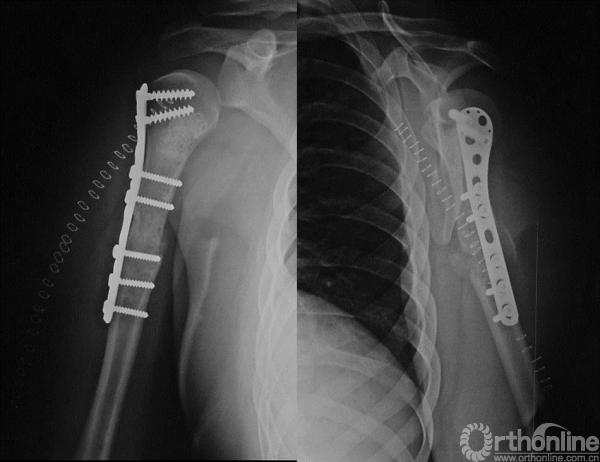

图13-5 病例一术后X线平片正侧位

术后病理报告示“倾向于侵袭性骨母细胞瘤”。

患者术后4个月发现原手术切口出现包块。

图13-6 病例二术后X线平片正侧位

术后病理示骨囊肿。